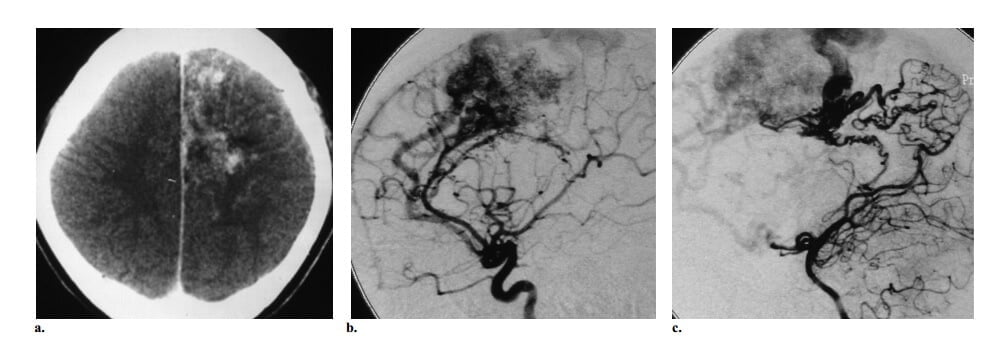

Hình 4: AVM kiểu tăng sinh ở bệnh nhân nữ 27 tuổi có bệnh sử đau đầu 6 năm và động kinh. (a) Axial CT cản quang thấy tổn thương bắt quang mạch máu ở thùy trán cạnh đường dọc giữa trái với vùng đồng đậm độ khu trú bên trong thể hiện nhu mô não bình thường xen kẽ trong nidus. (b, c) Chụp động mạch cảnh trong trái thế nghiêng (b) và động mạch cột sống trái (c) thấy nidus được cấp máu từ các nhánh của cả hai động mạch não trước và nhánh thể chai sau trái, với cấp máu màng mềm từ các nhánh của động mạch não sau trái và dẫn lưu tĩnh mạch sớm vào các tĩnh mạch vỏ não trán cạnh đường dọc giữa, các dấu hiệu khẳng định chẩn đoán AVM. Ghi nhận các vùng thấu quang trong nidus phù hợp với tổn thương kiểu tăng sinh.

Hình 6: CAMS type 2 ở bé gái 7 tuổi có từng đợt chảy máu lợi tái phát do mọc răng hàm trái. (a) Coronal CT (cửa sổ xương) thấy tổn thương hủy xương trong cầu ổ răng của xương hàm trên trái. (b, c) Chụp động mạch cảnh ngoài (b) và động mạch cảnh trong (c) thấy AVM xương mặt được cấp máu bởi các nhánh hàm trong và động mạch mặt ngang, dẫn lưu về túi tĩnh mạch trong xương (mũi tên ở b). Dấu hiệu này tương ứng với tổn thương hủy xương thấy ở a và được chứng minh là nguồn chảy máu của bệnh nhân. Cũng ghi nhận một AVM thần kinh thị trái, vì vậy cho phép chẩn đáon AMS type 2 Trong trường hợp này, thuyên tắc mạch cấp cứu của AVM mặt được thực hiện để làm ngừng chảy máu.